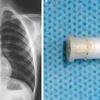

33-letni moški je prišel na urgenco zaradi hudo bolečega in oteklega penisa. Vzrok za stanje sta bila jeklena kroglična ležaja, ki sta vse bolj stiskala njegovo moškost. 14 dni pred tem si ju je nataknil na penis in ju ni mogel več sneti. Ko je moški poiskal pomoč, je bilo že precej hudo.

Pojavili so se predhodni znaki gangrene. Ležaja sta " zadavila" koren penisa. To pomeni, da v tkivu ni bilo krvi. Gangrena je odmrtje tkiva, ki nastane zaradi nezadostne prekrvitve, lahko jo spremlja tudi okužba. Zaradi nenavadne prakse samozadovoljevanja bi lahko prišlo do hudega zapleta, nenazadnje tudi do emputacije organa, opozarjajo zdravniki.

Moški je najprej prejel injekcijo za blažitev otekline, kirurg je poskusil s kleščami, vendar zaman. Sledil je, kot so zapisali, skrajni ukrep, ko je moral zdravnik poprijeti za industrijsko krožno žago za rezanje kamna. Ob tem so mu s hladno solno kopeljo hladili penis. Z Boschevo GDC 120 žago, katere rezilo se zavrti vrti do 200 krat na sekundo, so rezali 15 minut, preden so jekleni ležaji popustili, povzema DailyMail.

Zdravnikom je torej uspelo, oteklina je upadla že po dveh dneh. Po dveh tednih je že poročal o jutranj erekciji, so zapisali. 33-letnik iz New Delhija sedaj obiskuje psihiatra.